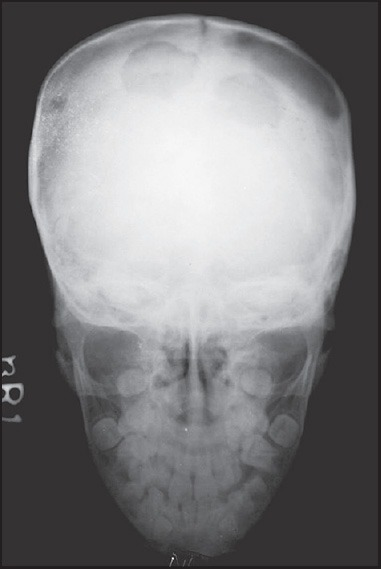

Lateral skull radiograph demonstrating a solitary 'punched-out' lytic lesion in the parietal bone characteristic of Langerhans cell histiocytosis (eosinophilic granuloma). The lesion has sharp, well-defined margins with a 'beveled edge' (inner table destroyed more than outer). There is no sclerotic rim or periosteal reaction. This appearance in a child is virtually pathognomonic for LCH.